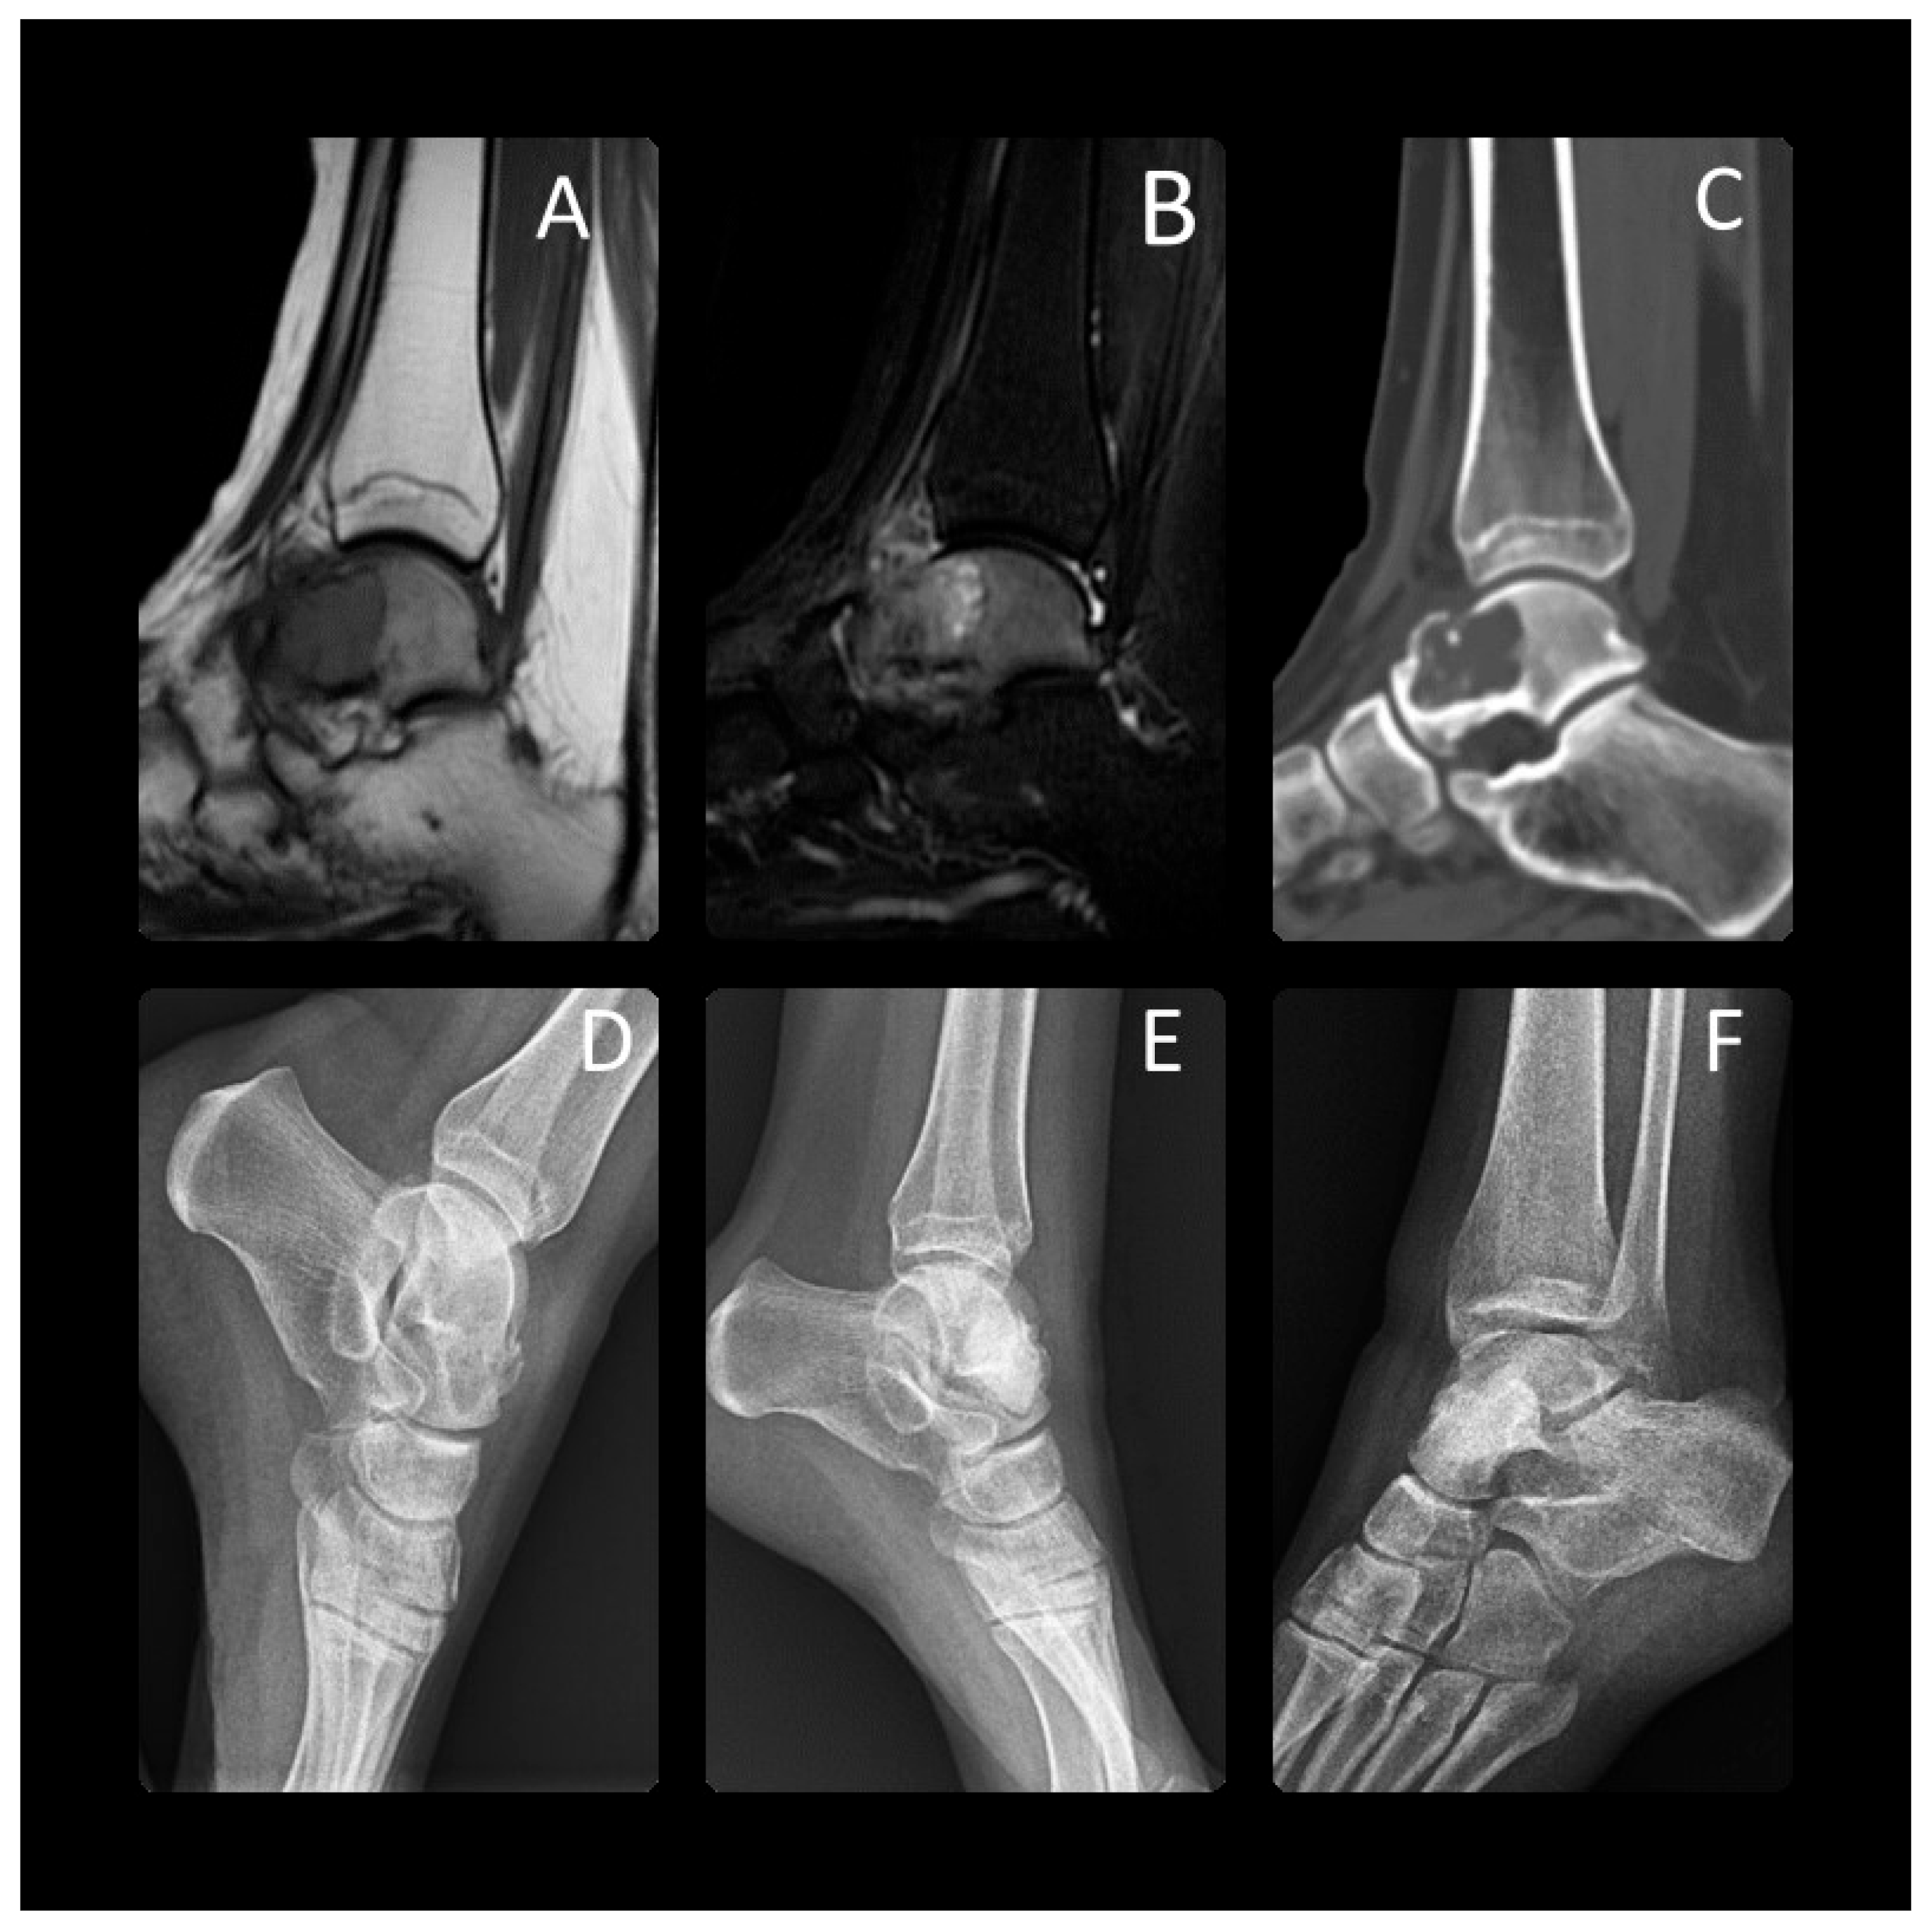

Figure 1. At the age of 17 years, this patient presented with chondroblastoma of the talus. A preoperative Tl-weighted (A) and T2-weighted (B) MRI, CT (C) and X-ray (D) radiograph showed a 3 cm lucent lesion within the talar neck. Expansile periosteal reaction was identified. In the distal part of the talus, particularly in the neck and the area near to the talonavicular joint, a microfracture was observed, along with considerable bone edema. This was treated with aggressive curettage and bone cementing. The final radiographs were taken 1 year (E) and 3 years (F) after surgery. Skeletal maturity shows the lesion had completely healed.